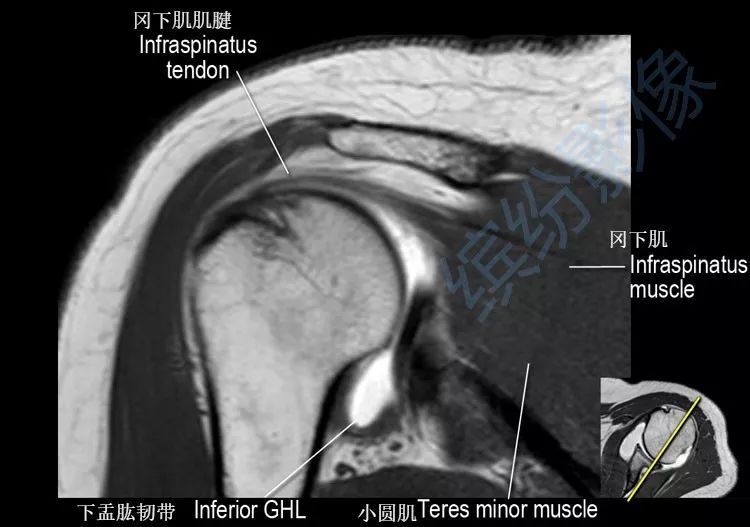

肩关节斜冠状面mr断层解剖